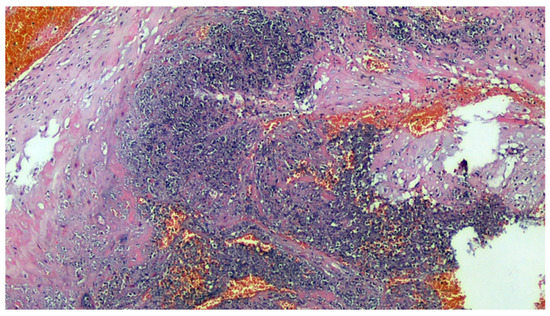

Figure 4.

Deciduitis with large foci of necrosis and massive infiltration of mainly granulocytic inflammatory elements (acute deciduous, H&E, 200×) in the placenta of a COVID-positive mother.